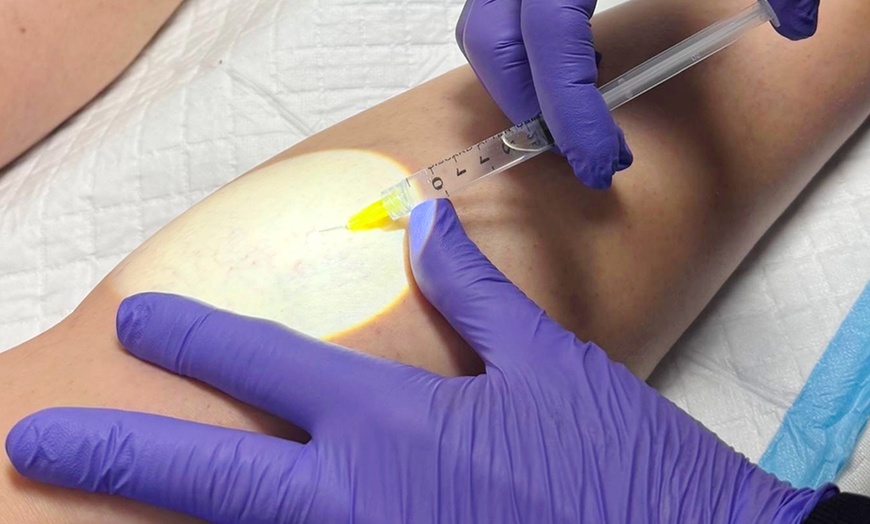

Sclerotherapy Spider Vein Injections (10cc) with ultrasound use a fine needle to inject a specialized solution that safely collapses and fades visible spider veins. The ultrasound guidance ensures precision and effectiveness, targeting problem veins beneath the skin for smoother, clearer, and healthier-looking legs.